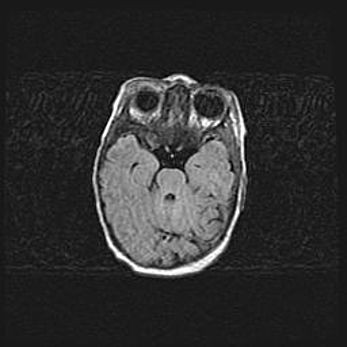

Аномалия Денди-Уокера. Признаки гипоплазии мозолистого тела.

Возраст: 5 месяцев 3 дня

Вес: 5550 г

Пол: мужской

Окружность головы: 39 см

Срок гестации: 40 недель

Аномалия Денди-Уокера – это порок развития головного мозга, для которого характерна триада симптомов: гипотрофия или аплазия червя мозжечка и/или полушарий мозжечка, расширение четвёртого желудочка с формированием ликворной кисты задней черепной ямки, гипертензионная гидроцефалия различной степени.

Гипоплазия мозолистого тела относится к дефектам внутриутробного этапа развития мозговой ткани, возникающим в процессе закладки структур головного мозга, что происходит на начальных этапах развития эмбриона.